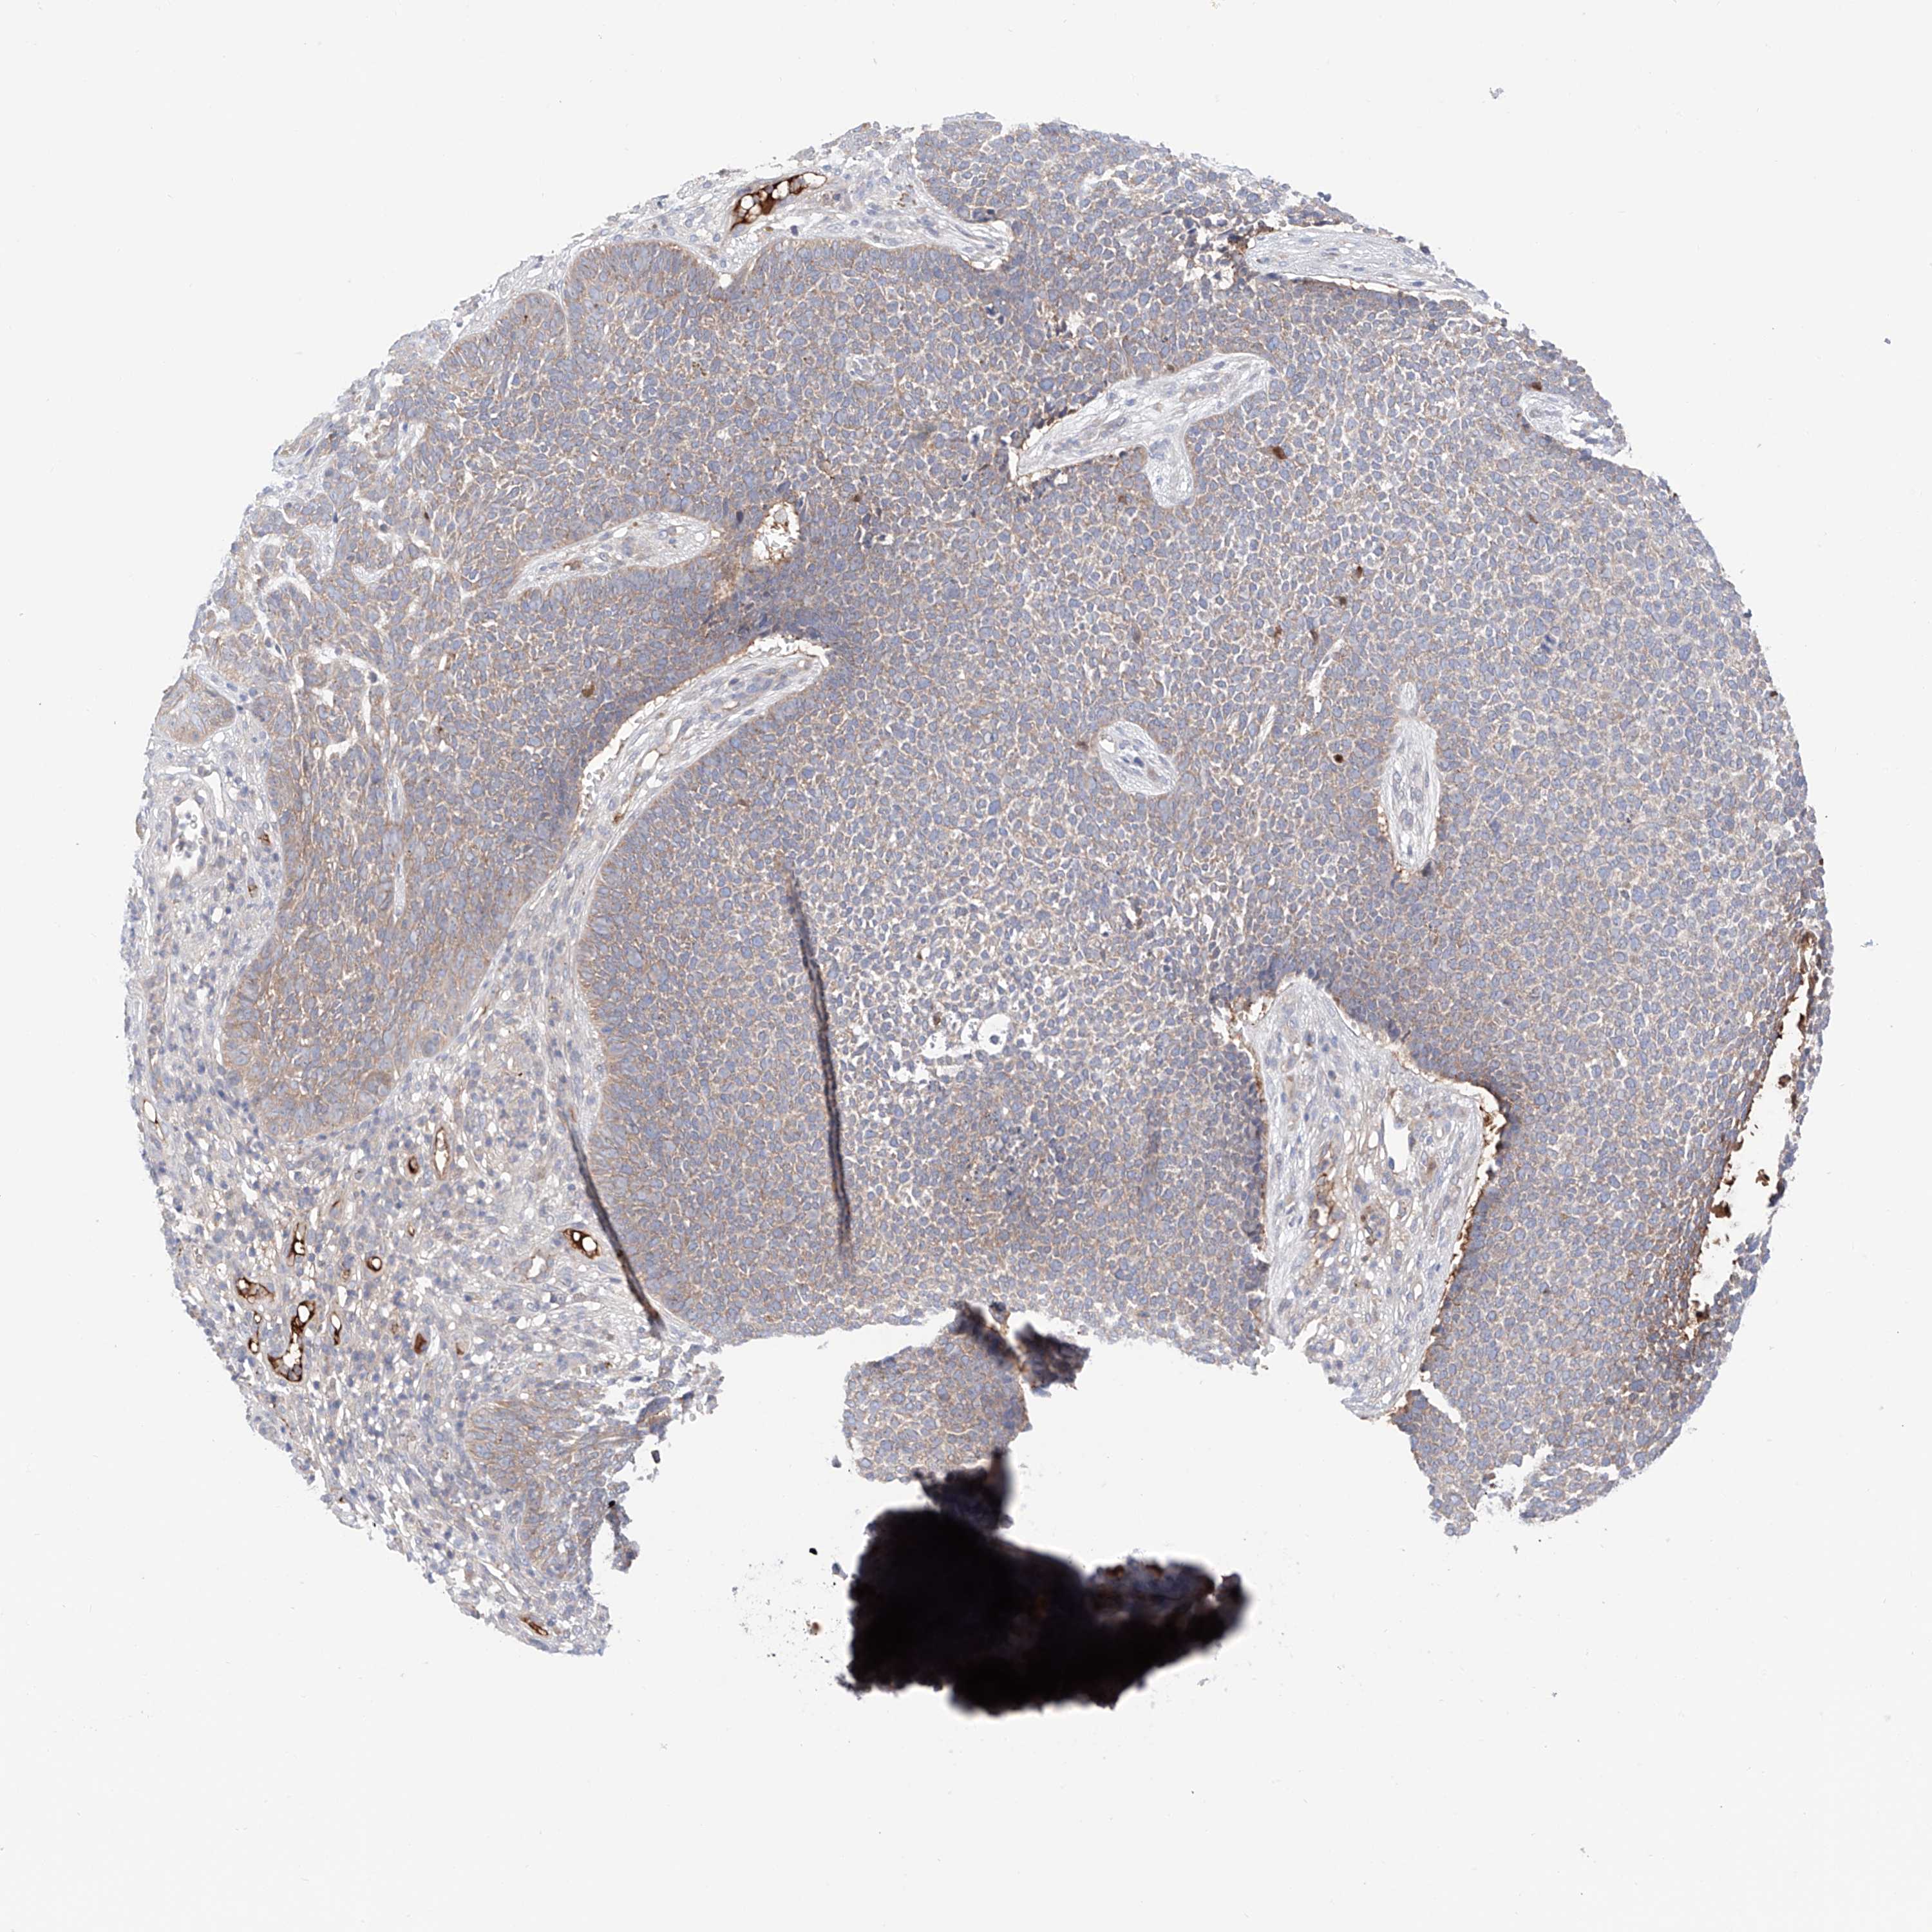

SKIN CANCER - Protein expressioni

A mouse-over function shows sample information and annotation data. Click on an image to view it in a full screen mode. Samples can be filtered based on level of antibody staining by selecting one or several of the following categories: high, medium, low and not detected. The assay and annotation is described here.

Antibody stainingi

Antibody staining in the annotated cell types in the current human tissue is reported as not detected, low, medium, or high, based on conventional immunohistochemistry profiling in selected tissues. This score is based on the combination of the staining intensity and fraction of stained cells.

Each image is clickable and will lead to virtual microscopy that enables deeper exploration of all samples and also displays staining intensity scores, fraction scores and subcellular localization as well as patient and tissue information for each sample.

Antibody HPA030646

Squamous cell carcinoma, NOS

Squamous cell carcinoma, metastatic, NOS